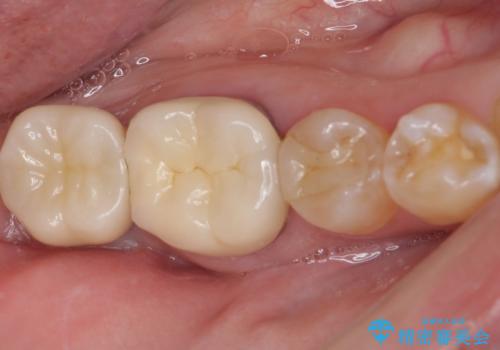

[20代男性] インプラント 失った歯の治療

![[20代男性] インプラント 失った歯の治療の症例 治療後](https://seimitsushinbi.jp/wp/wp-content/uploads/2019/11/IMG_9922-1-500x350.jpg?v=1574736466)